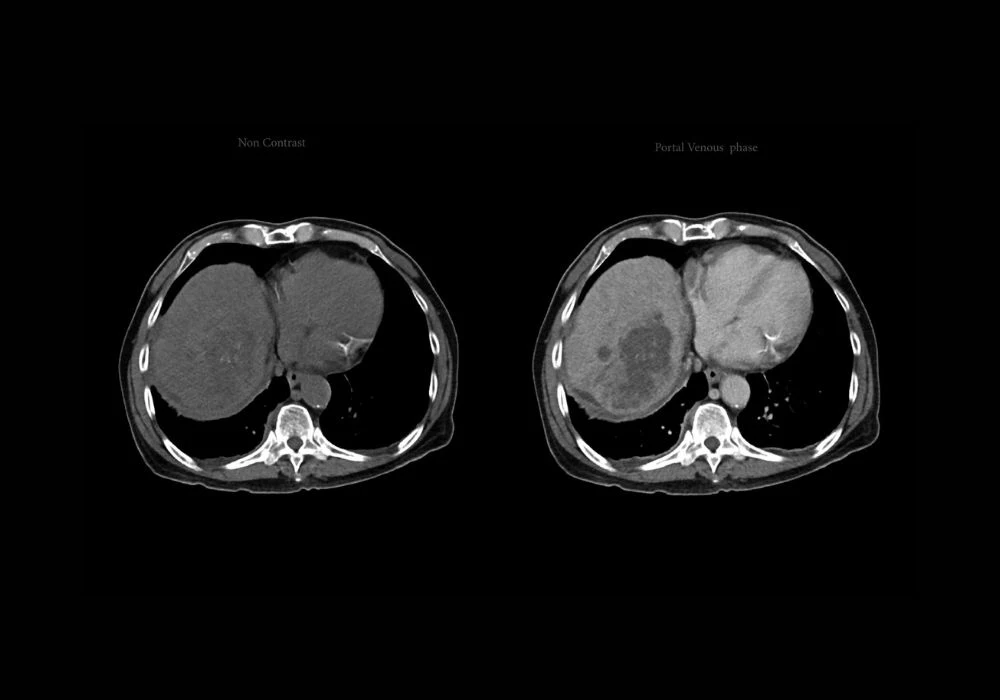

Hepatocellular carcinoma (HCC) remains a major global health challenge, being the third leading cause of cancer-related mortality. Its aggressive variants, particularly the proliferative subtype, are associated with poor prognoses and high recurrence rates post-surgery. Traditional diagnostic approaches rely heavily on invasive methods like histopathology, which come with inherent risks. While dynamic contrast-enhanced MRI (DCE-MRI) offers a noninvasive alternative, its full diagnostic potential is underutilised due to the subjective nature of image interpretation. To address these challenges, a novel deep learning (DL) model integrating self-supervised learning (SSL) with dynamic radiomics has been developed. This model enhances the precision and consistency of identifying proliferative HCC subtypes from multi-sequence DCE-MRI, offering new avenues for personalised treatment planning.

Dynamic radiomics enables the extraction of time-resolved imaging features from DCE-MRI, offering deeper insights into tumour behaviour. However, conventional radiomics relies on manual annotation of regions of interest, which is both labour-intensive and prone to variability. To overcome this limitation, the pHCC-SSL model integrates a self-supervised approach that allows autonomous learning from raw imaging data without manual labelling. At its core, the model employs a sample-weighted full-convolution mask autoencoder (SW-FCMAE) to extract deep features, minimising redundancy and enhancing feature diversity.

The architecture follows a two-stage process. Initially, the model undergoes SSL pre-training to develop a foundational understanding of imaging characteristics. This is followed by a task-specific fine-tuning phase, where deep dynamic features are constructed by aggregating temporal data across multiple MRI sequences. These features are then processed using a self-attention mechanism, enabling the model to learn patterns indicative of tumour proliferation over time. This dynamic learning capability significantly enhances the model’s diagnostic accuracy.

The pHCC-SSL model was trained and validated on data from 381 patients across two medical centres, split into training, internal testing and external testing sets. The results demonstrated robust performance, with the model achieving an AUC of 0.91 in the internal test set and 0.94 in the external test set. This outperformed models that did not utilise SSL, highlighting the benefit of the pre-training phase. Comparative assessments against single-sequence prediction models further confirmed the superior accuracy of the multi-sequence pHCC-SSL model.

In addition to quantitative metrics, the model’s interpretability was enhanced using class activation mapping (CAM), which visually identified tumour regions most influential in predictions. The heat maps revealed focused activity within tumour zones, particularly in sequences that captured key vascular characteristics, supporting the model’s reliability in clinical evaluation.